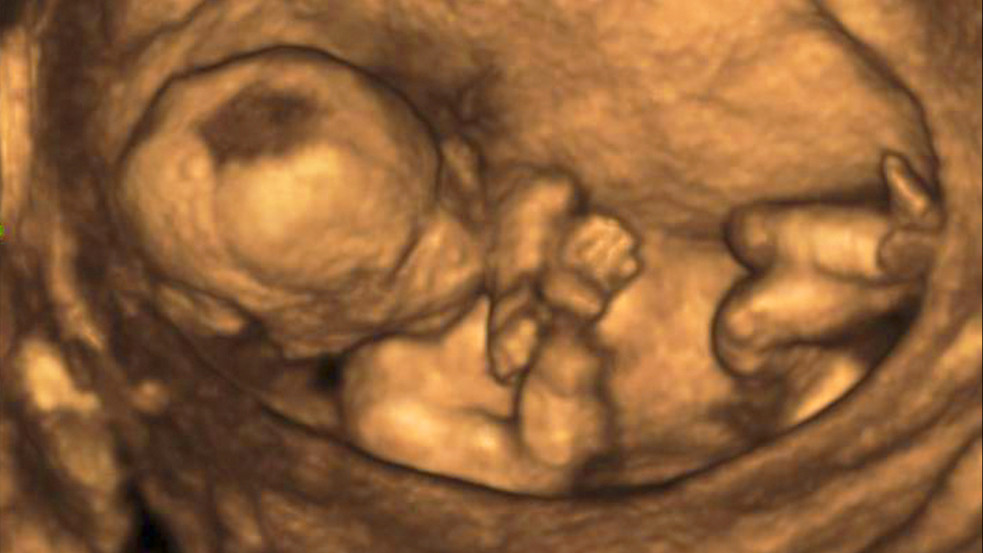

Illusztráció( Forrás: Shutterstock/PuzzlePix)